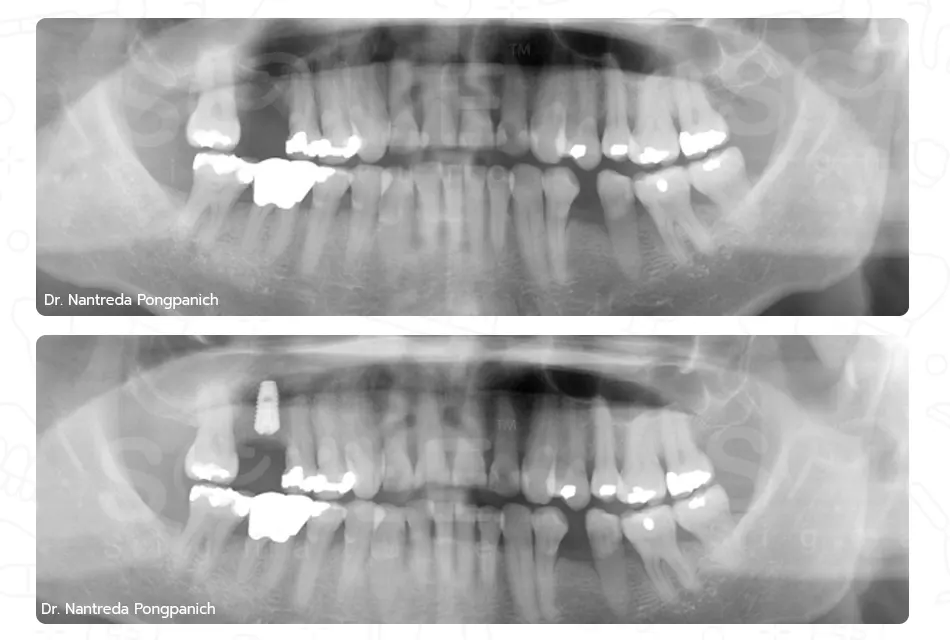

เฉพาะทางสาขาสาขาทันตกรรมรากเทียม, สาขาศัลยศาสตร์ช่องปาก และแม็กซิลโลเฟเชียล